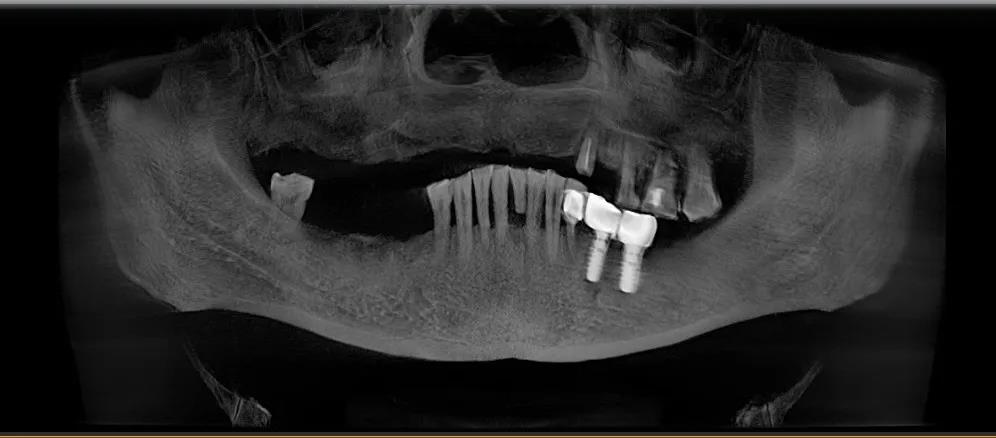

那时候因为年龄偏大,加上技术发展没有到,不能在上颌种植满口牙,只能在左下颌种了两颗新牙,正好对着左上颌残存的四颗老牙。

△第一次种植

2020年1月8日,我和90岁的老亲家先后动了手术。我的手术,上颌拔牙4个,同时打钛钢基钉6个,再安装12个牙冠,用时2个钟头;90岁的兰淑香打钢钉3个,不痛不肿,比我更顺利。

1月19日,我又在右下颌打进2颗钛钢钉,用时20分钟,一个月后再安装牙冠。